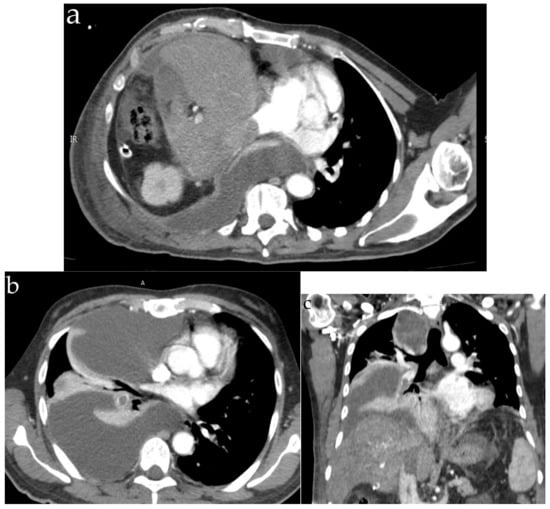

5.2. Diagnosis

| Computer tomography | Small amount of air in the main pulmonary artery, on the right heart or systemic veins; in severe cases, pulmonary hypertension and right heart strain are found | Ground-glass opacities, interlobar septal thickening with the pattern of “crazy paving” | Diffuse bilateral ground-glass opacities | Bilateral lung nodules, located mainly in the peripheral lung areas and in the lower lobes, mediastinal or hilar lymphadenopathy, a dilated pulmonary branch (mycotic aneurysm) and feeding vessel sign | The classic finding (affected centrilobular arteries) is an image of “tree-in-bud”; in cases where the main arteries are affected, the findings are filling defects that resemble acute or chronic pulmonary emboli |